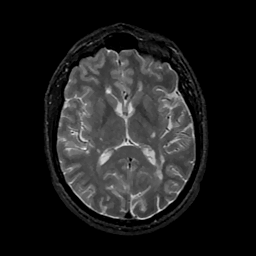

MR Study #11, May 5, 1991 -- Slice #27